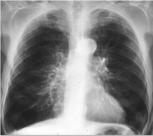

Рентгеноскопия и рентгенография легких. Рентгенологические призна-

ки хронического бронхита выявляются лишь у длительно болеющих, при этом характерно усиление и деформация легочного рисунка по петлисто-ячеистому

типу, повышение прозрачности легочных полей, расширение теней корней легких. В ряде случаев можно видеть утолщение стенок бронхов вследствие перибронхиального пневмосклероза.